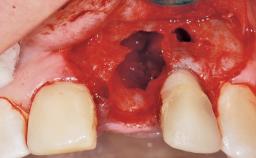

Immediate Flapless Placement of an Implant in a Maxillary Right Lateral Incisor Site

This 43-year-old male patient, a non-smoker, came to our practice because of a fracture of tooth 12 caused by a bicycle accident. Due to the combined para- and infrabony crown and root fracture, tooth extraction, and subsequent implant placement were suggested to the patient as the therapy of choice. The patient had high esthetic expectations with regard to the treatment outcome and asked for an immediate fixed provisional restoration. His individual esthetic risk profile summed up to a medium esthetic risk.

Soft Tissue Anatomy Intact Defective

Bone Volume Horizontally and vertically sufficient Horizontally deficient Deficient vertically or deficient vertically AND horizontally

Socket Integrity Sufficient, with intact bone walls

Bone Volume Sufficient, with intact walls